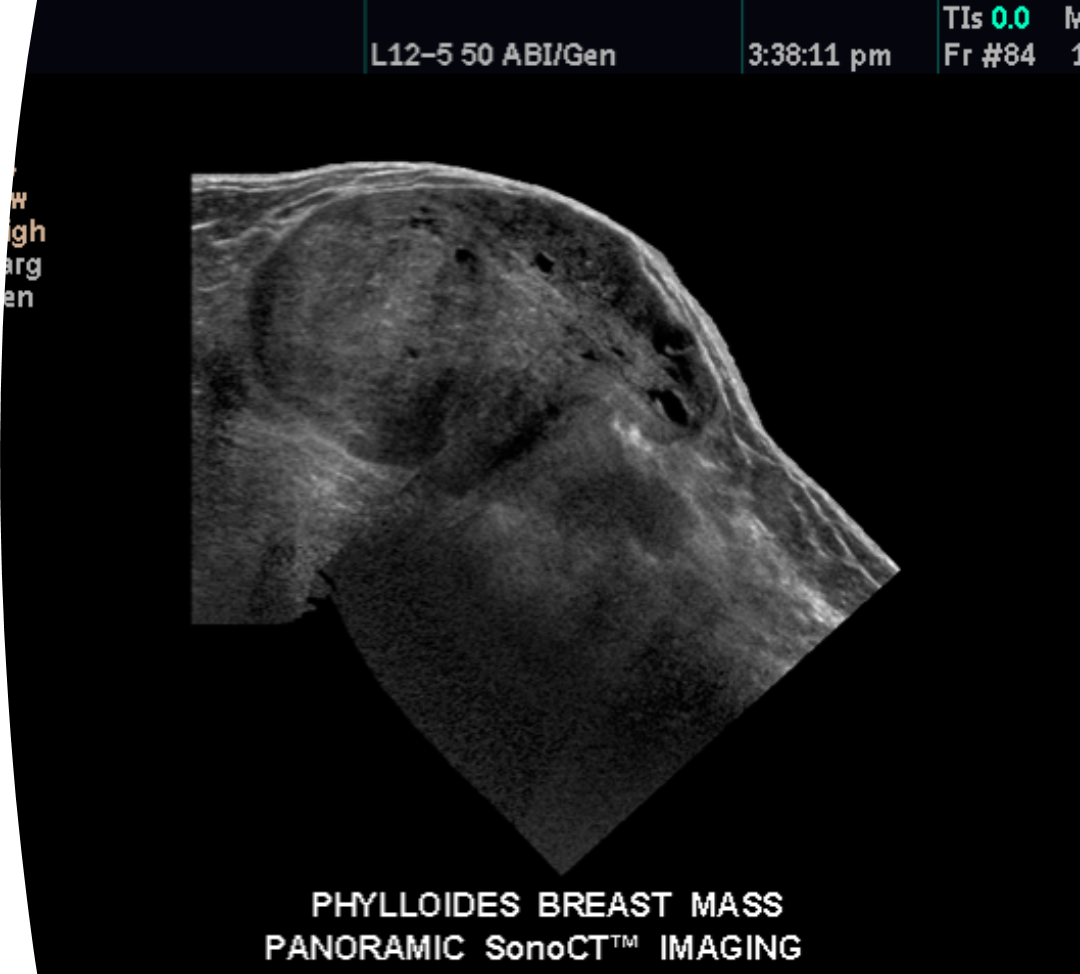

What is this image showing?

phyllodes